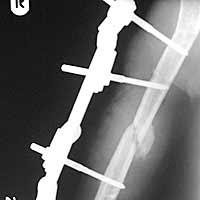

Slika 1. Mitković spoljašnji fiksator primenjen

u lečenju nezaraslog preloma humerusa

Bez obzira na prethodni način lečenja preloma humerusa svi pacijenti su lečeni metodom spoljne fiksacije Mitković unilateralnim spoljnim fiksatorom (Slika 1.) (Trafix, Niš) (13, 14). Medicinska dokumentacija kao i pre i postoperativne radiografije su uredno praćene.

Dobro zarastanje, verifikovano radiološki, konstatovano je kod 9 (81,8%) pacijenata (Slika 3). Do zarastanja nije došlo kod 2 (18,2%) pacijenta od 11 pacijenata tretiranih metodom spoljne fiksacije. Prosečno vreme zarastanja iznosilo je 3,6 meseci (3-5 meseci).

Slika 3. Radiografija na kraju lečenja

nezaraslog preloma humerusa